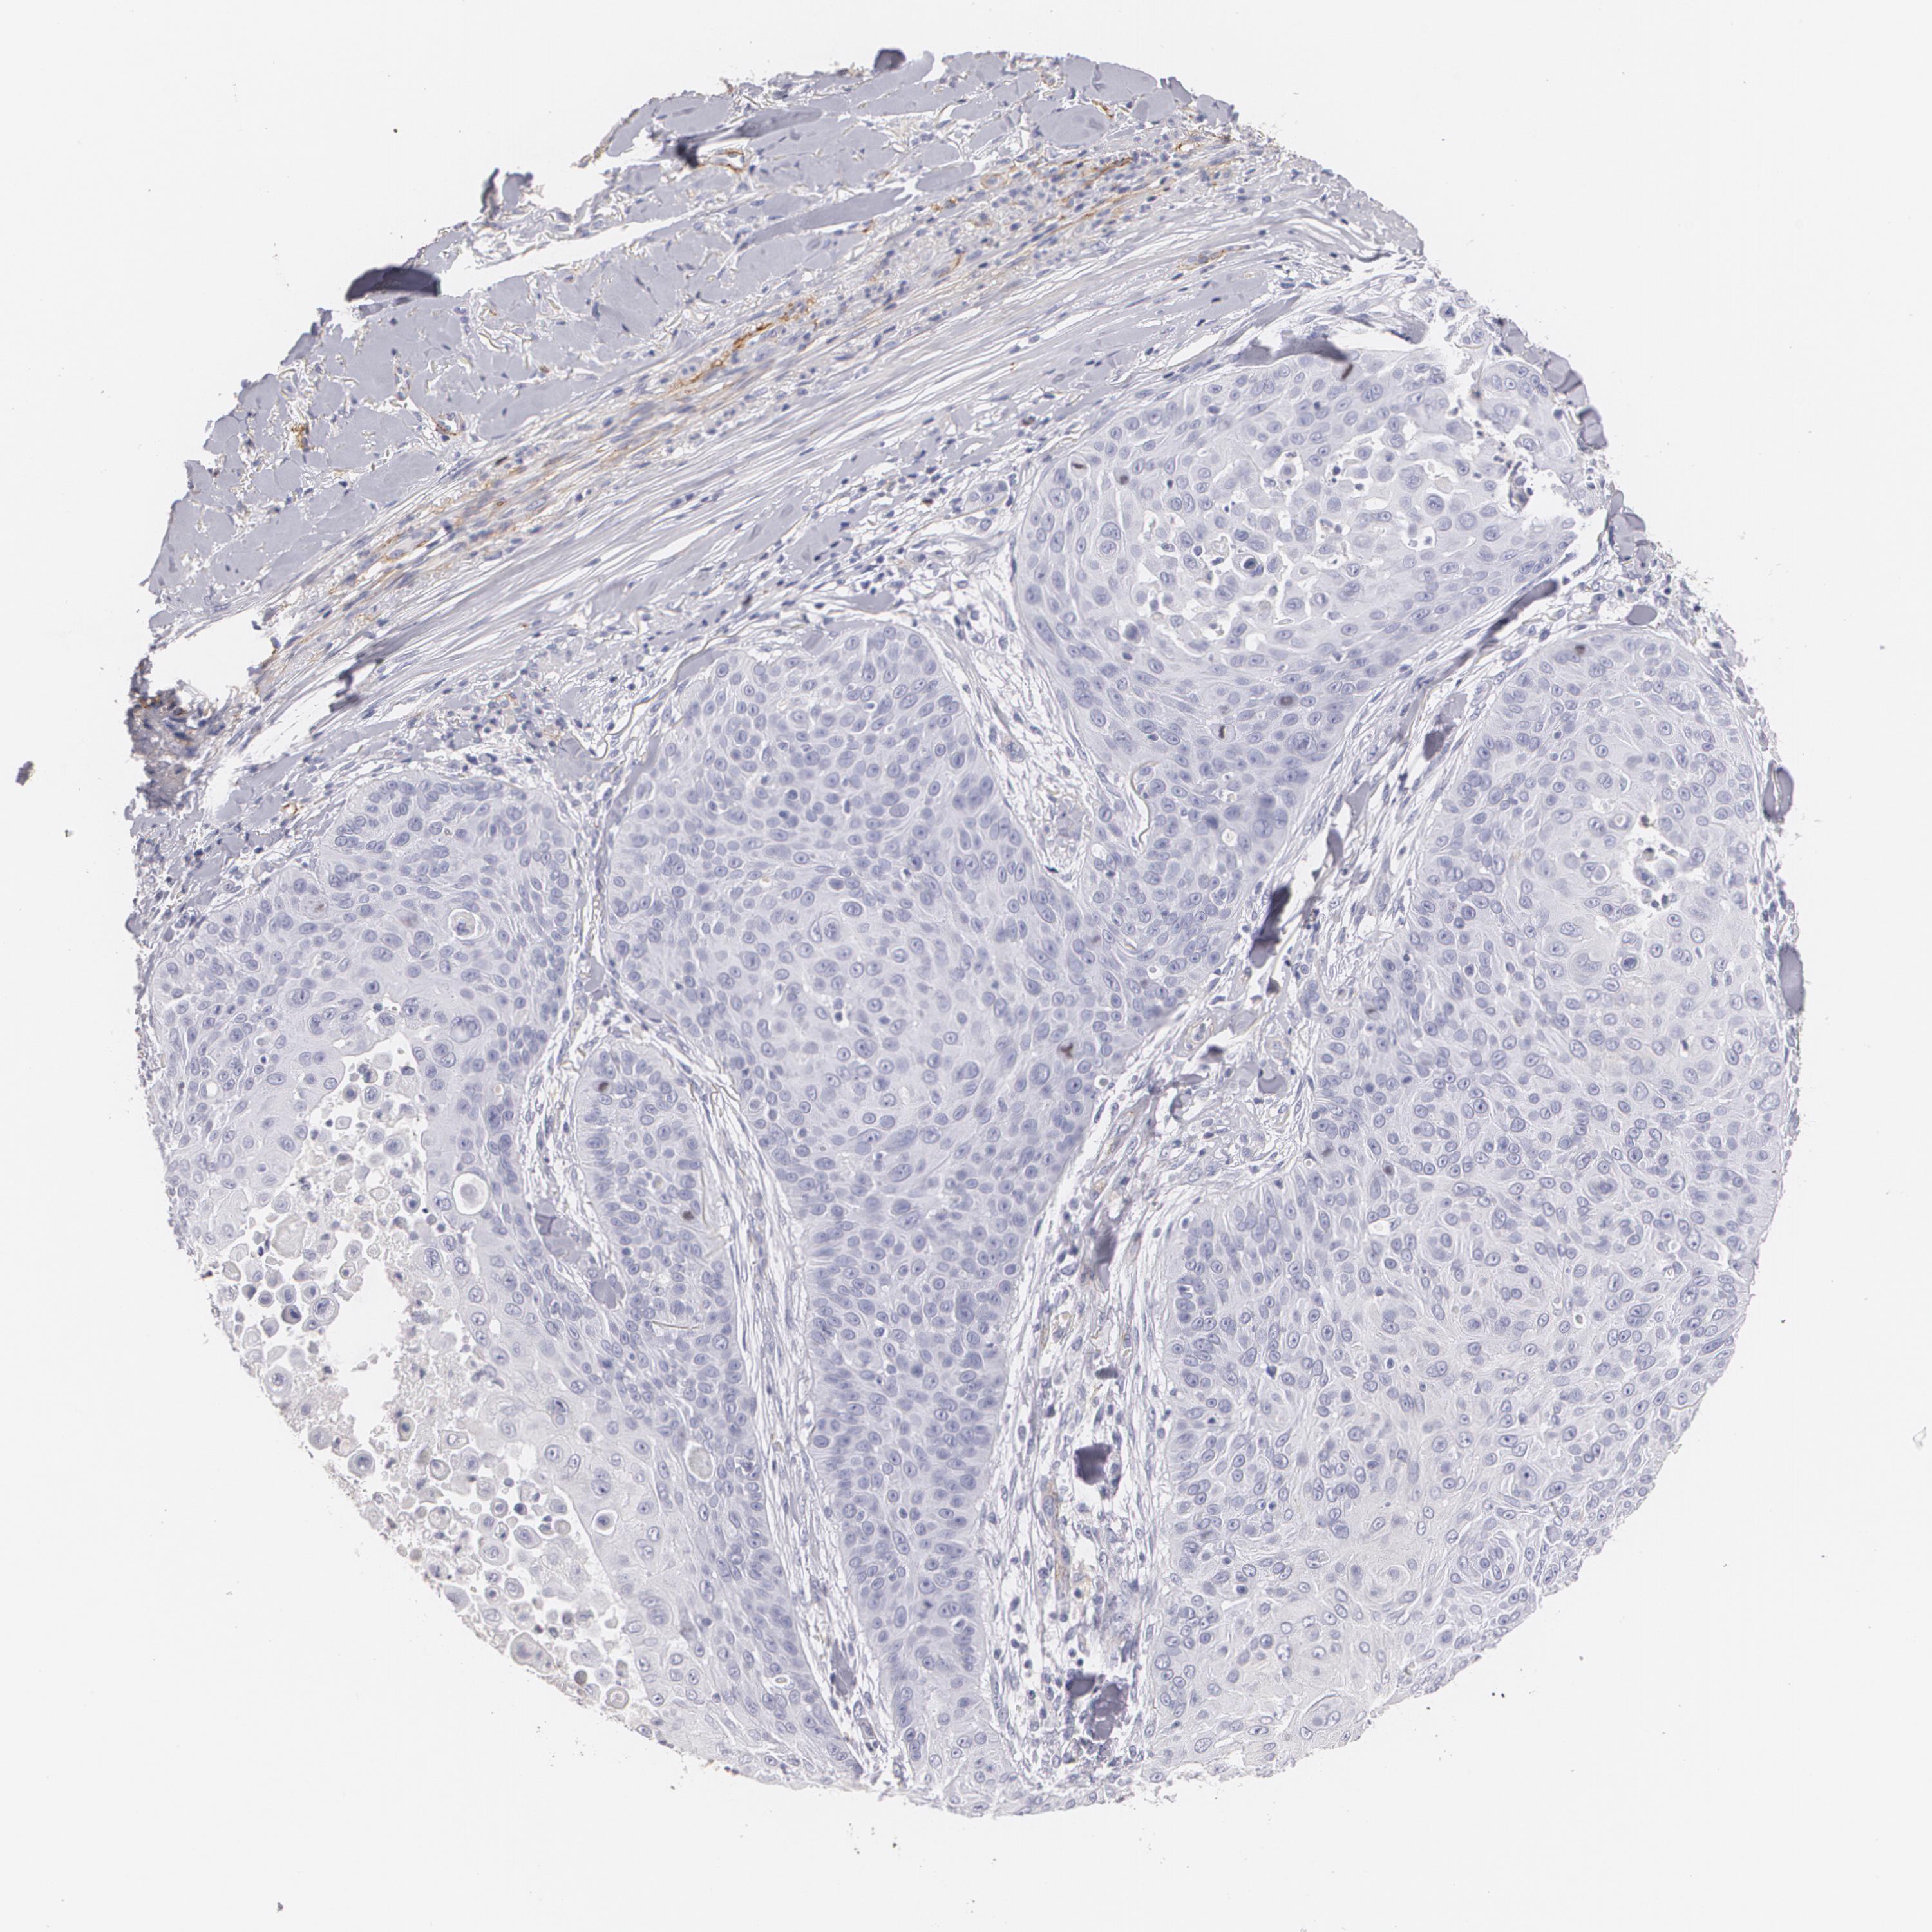

SKIN CANCER - Protein expressioni

A mouse-over function shows sample information and annotation data. Click on an image to view it in a full screen mode. Samples can be filtered based on level of antibody staining by selecting one or several of the following categories: high, medium, low and not detected. The assay and annotation is described here.

Each image is clickable and will lead to virtual microscopy that enables deeper exploration of all samples and also displays staining intensity scores, fraction scores and subcellular localization as well as patient and tissue information for each sample.

Antibody HPA004765

Staining

High

Medium

Low

Not detected

Intensity

Strong

Moderate

Weak

Negative

Quantity

>75%

75%-25%

<25%

None

Location

Nuclear

Cytoplasmic/membranous

Cytoplasmic/membranous,nuclear

Squamous cell carcinoma, NOS

Basal cell carcinoma